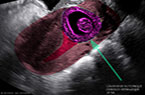

Grossesse extra-utérine de la portion moyenne de la trompe gauche, évolutive et âgée de 9 SA et 1 jour Grossesse extra-utérine de la portion moyenne de la trompe gauche, évolutive et âgée de 9 SA et 1 jour Grossesse extra-utérine de la portion moyenne de la trompe gauche, évolutive et âgée de 9 SA et 1 jour